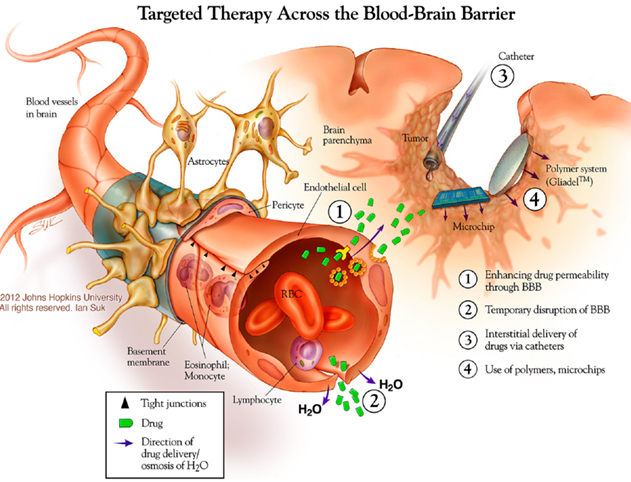

55 brain levels of thought

58 brain Septum attacks on Sept 11,2001

Septum pellucidum – Wikipedia

The septum pellucidum (translucent hedge) is a thin, triangular, vertical double membrane separating the anterior horns of the left and right lateral ventricles of …

Know your brain: Septum — Neuroscientifically Challenged

Dec 8, 2016 – The term septum, when used in reference to the brain (it is a common anatomical term used to refer to a partition), indicates a subcortical …

Know your brain: Septum

Know your brain: Septum

Know your brain: Septum ordered attack for September 11, 2001